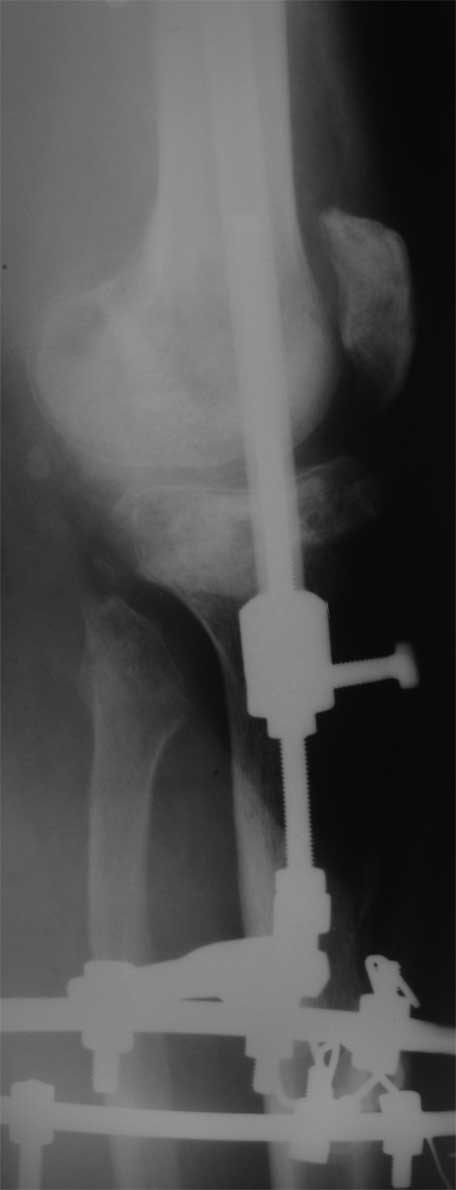

2. Хотелось бы увидеть снимки раннего периода, лучше после травмы, а также КТ. Интересует целостность плато б/б кости. По представленным

снимкам возникает подозрение, что наружный мыщелок отделен. Или это так кажется?

У пациента жестокая эквинусная контрактура голеностопного сустава и почти наверняка - разгибательная в коленном суставе.

Не поврежден ли малоберцовый нерв?

> Хотелось бы увидеть снимки раннего периода, лучше после травмы, а также КТ. Интересует целостность плато б/б кости. По представленным

- нет, скорее всего не кажется, вероятно он отделен, но, скорее всего живой и неподвижный (иначе рассосался бы)